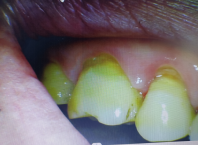

出现这种情况也不要紧张,如果缺损的牙体组织比较少,牙齿也没有敏感的症状,一般不需要特殊的处理。

泰安牙科

如果牙齿出现了吸冷风喝冷水有感觉的症状,就要及时进行治疗,临床上常见的办法便是充填治疗,若没有及时治疗,细菌一旦侵入,就容易损伤神经。